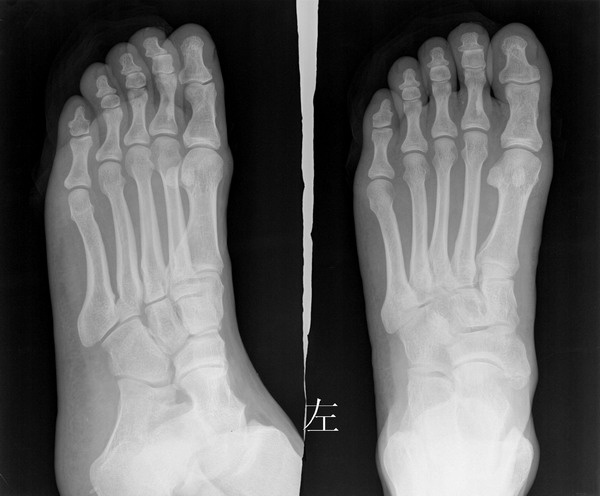

标题: X0829:大家帮忙看下左足第二近节趾骨是否正常?

男,38岁,外伤来诊.

好象第二近节趾骨基地部骨折吧

这是典型蜡油骨,我院门诊人群中经常见到,容易混淆.

骨岛

支持骨岛[内生骨瘤]

不能考虑骨岛吧,骨岛是髓质内的密质骨,大家是不是经常在胫骨上端常见这种现象,正常.应该没有临床症状.